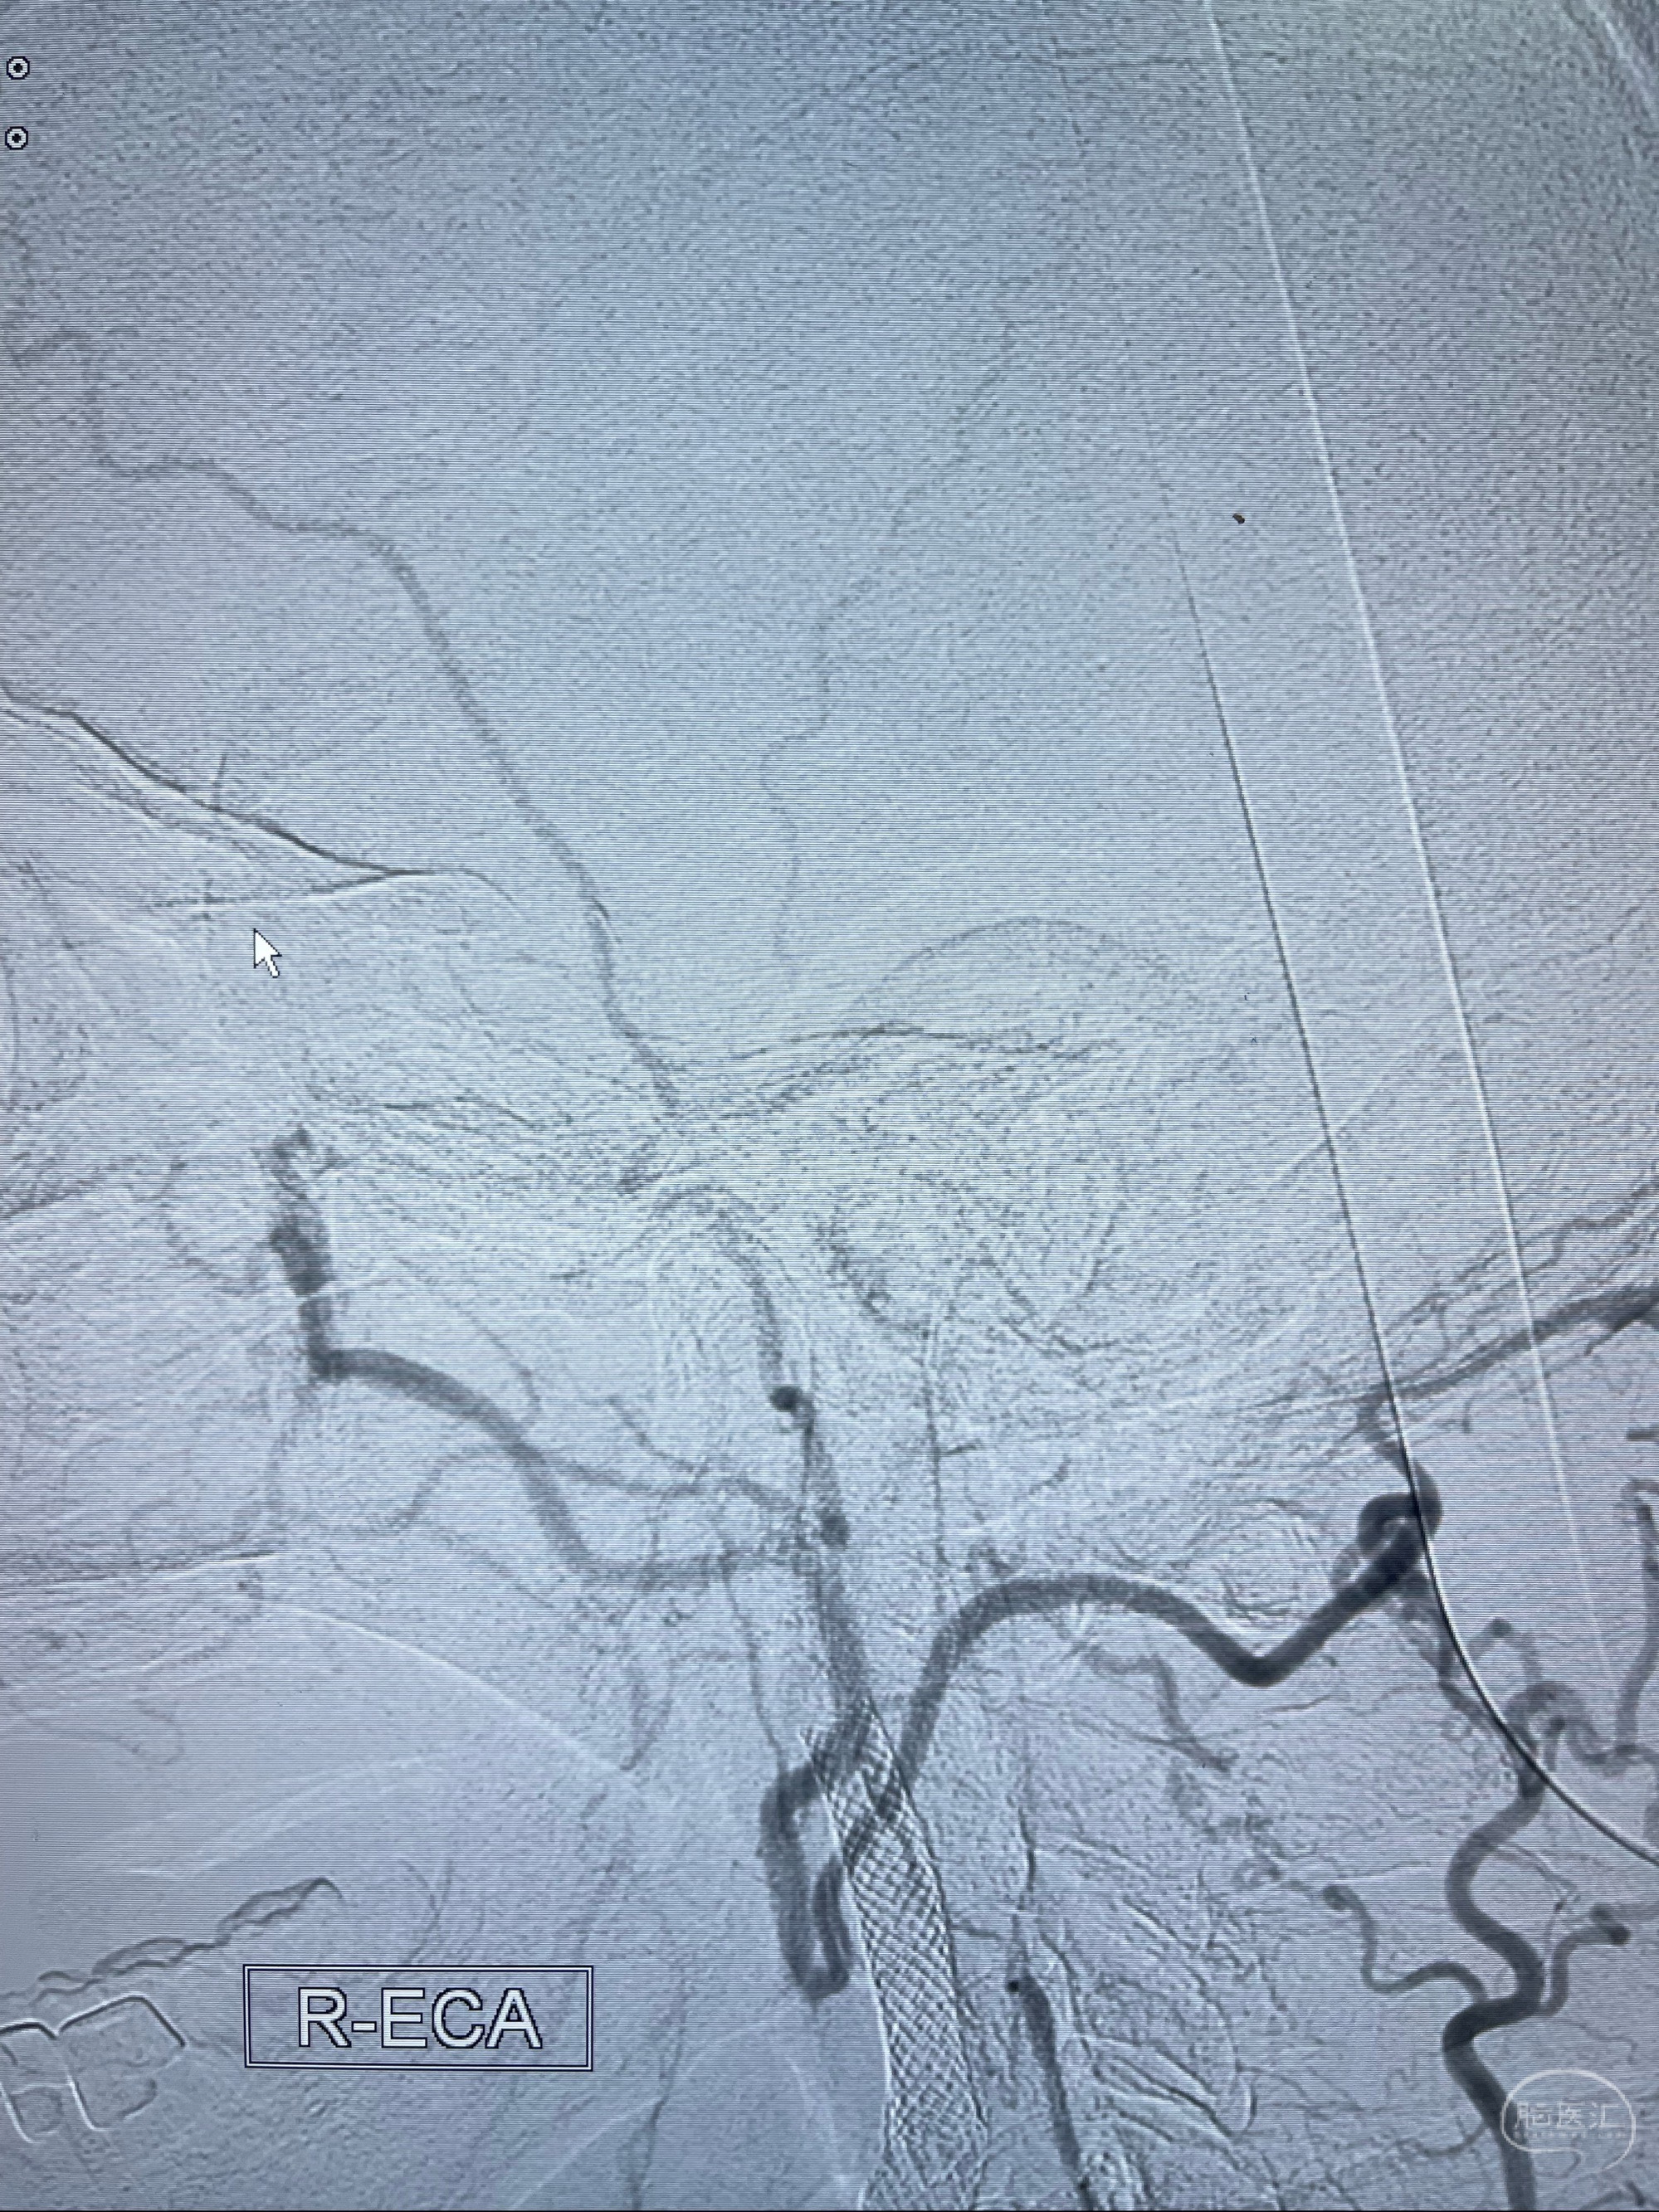

2023-07-10DSA:右侧颈内动脉岩骨段夹层伴中偏重度狭窄改变,左侧颈总动脉闭塞、右侧颈外动脉由右侧肋颈干甲颈干吻合代偿

箭头所示为颈内动脉岩骨段重度狭窄,结合MRI,考虑为肿瘤侵犯右侧颈内动脉

箭头以近至支架段管腔不规则狭窄

右侧椎动脉可见吻合代偿右侧颈外动脉